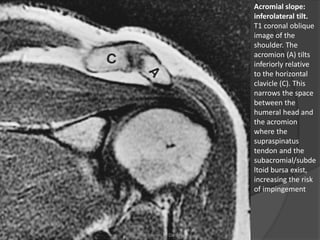

Acromial slope:

inferolateral tilt.

T1 coronal oblique

image of the

shoulder. The

acromion (A) tilts

inferiorly relative

to the horizontal

clavicle (C). This

narrows the space

between the

humeral head and

the acromion

where the

supraspinatus

tendon and the

subacromial/subde

ltoid bursa exist,

increasing the risk

of impingement